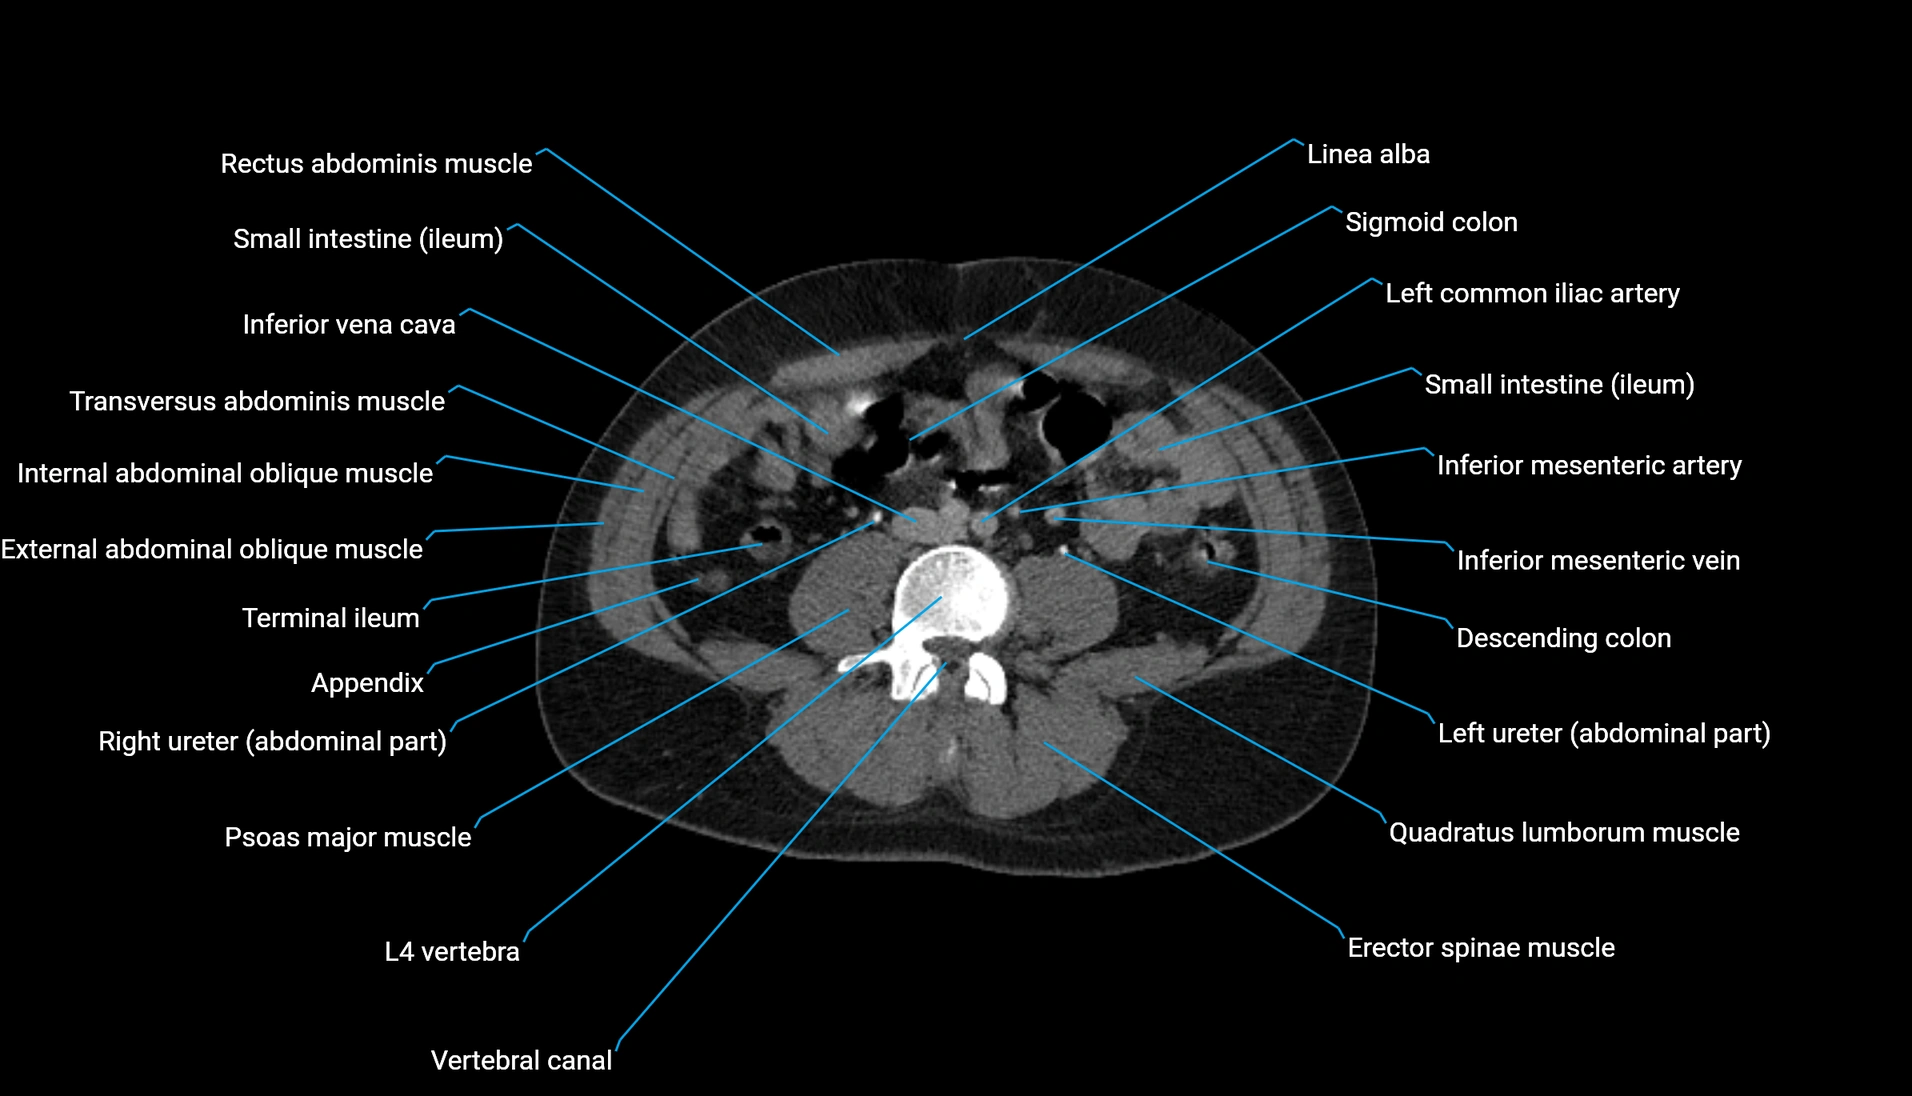

CT Appearance

Non-contrast CT:

-

Demonstrates cortical bone of acetabular rim in excellent detail

Detects fractures, dysplasia, retroversion, or bony overcoverage (pincer impingement)

3D reconstructions used in preoperative hip surgery planning

CT image